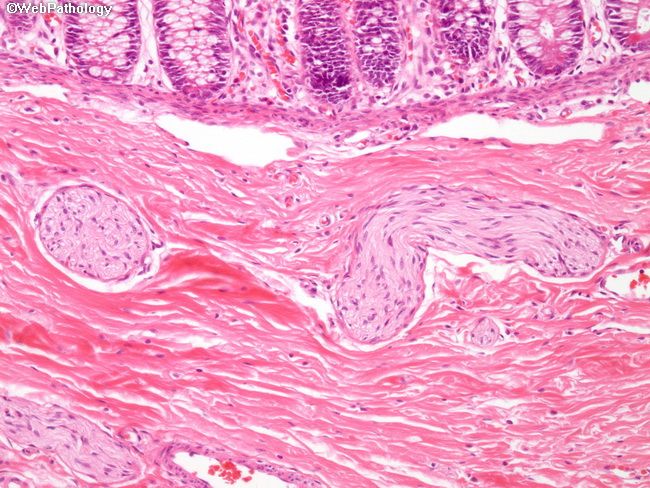

Болезнь гершпрунга нмо

Болезнь гершпрунга нмо 114 фото